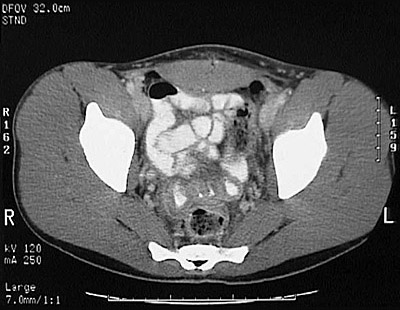

[S5] This is a normal pelvic CT scan with contrast demonstrating the right ilium and left ilium and sacrum and loops of small intestine and rectum and sigmoid colon and right external iliac vein and right external iliac artery and left external iliac vein and left external iliac artery and iliopsoas muscle and rectus abdominis muscle and gluteus medius muscle and gluteus maximus muscle and gluteus minimus muscle in the pelvis.